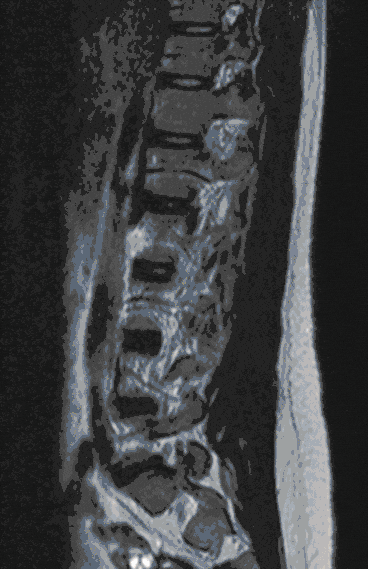

Herniated discs are among the degenerative spinal diseases and frequently occur in the lumbar and cervical spine, less frequently in the thoracic spine.

Herniated discs can manifest themselves as back or neck pain as well as radiating pain in the arms and legs or sensory disturbances. In severe cases, paralysis and disturbances in bladder and bowel control may occur.